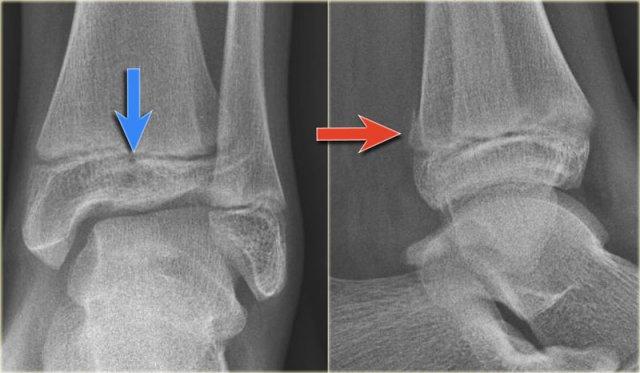

Các hình ảnh cho thấy một trường hợp gãy Weber B rõ ràng.

Trên tư thế thẳng (AP), đường thấu quang dạng tuyến tính là dấu hiệu gợi ý gãy tertius (mũi tên đỏ).

Dấu hiệu này xuất hiện do sự lệch trục nhẹ của mảnh gãy.

Tương tự, trong một số trường hợp, sự lệch trục có thể tạo ra một đường tăng tỷ trọng dạng tuyến tính.

Trong trường hợp này, có gãy Weber B kèm theo bong điểm bám mắt cá trong.

Đường tăng tỷ trọng trên tư thế thẳng (AP) gợi ý một mảnh gãy tertius lớn.

Gãy tertius này cũng có thể thấy trên tư thế nghiêng, nhưng trong nhiều trường hợp chúng ta cần kết hợp thông tin từ cả hai tư thế nghiêng và thẳng để chẩn đoán gãy tertius.